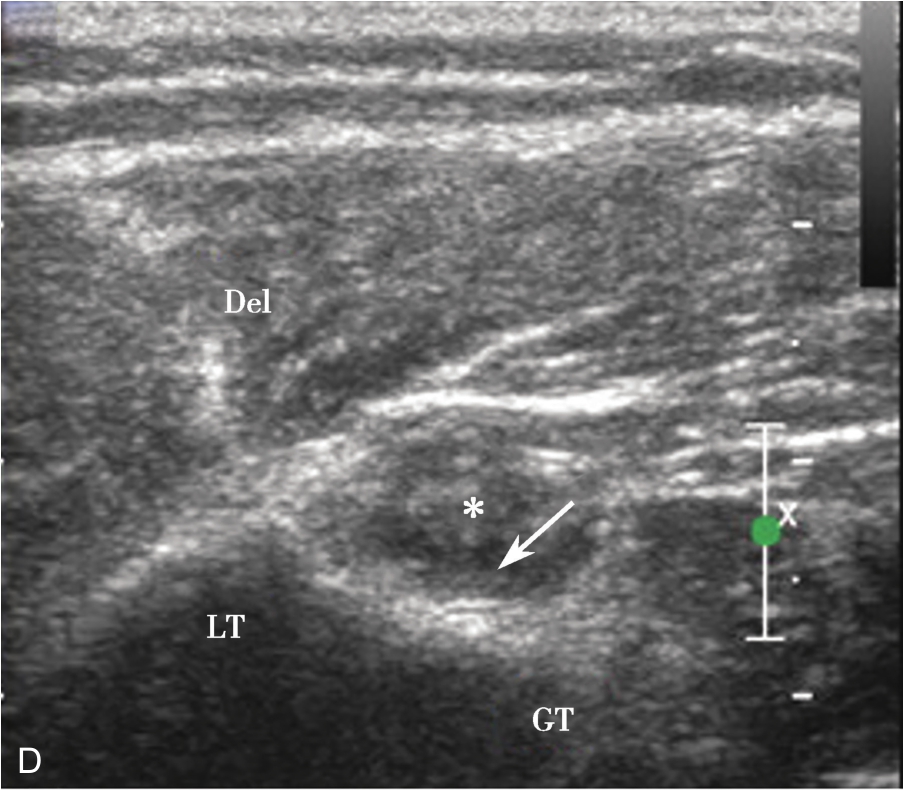

▲ 图2-1-10 超声引导下肩峰下-三角肌下滑囊造影图(三)

A.造影剂从滑囊(单箭头)及冈上肌腱撕裂处达肱骨头表面(双箭头),星号:滑囊撕裂处;B.冈上肌腱(SUP)回声不均匀,箭头:连续的滑囊,星号:滑囊回声中断,HH:肱骨头;C肱二头长头腱鞘内可见造影剂高增强(箭头);D:肱二头肌肌腱横断面(星号),腱鞘内造影剂(箭头);Del:三角肌;LT:肱骨小结节;GT:肱骨大结节